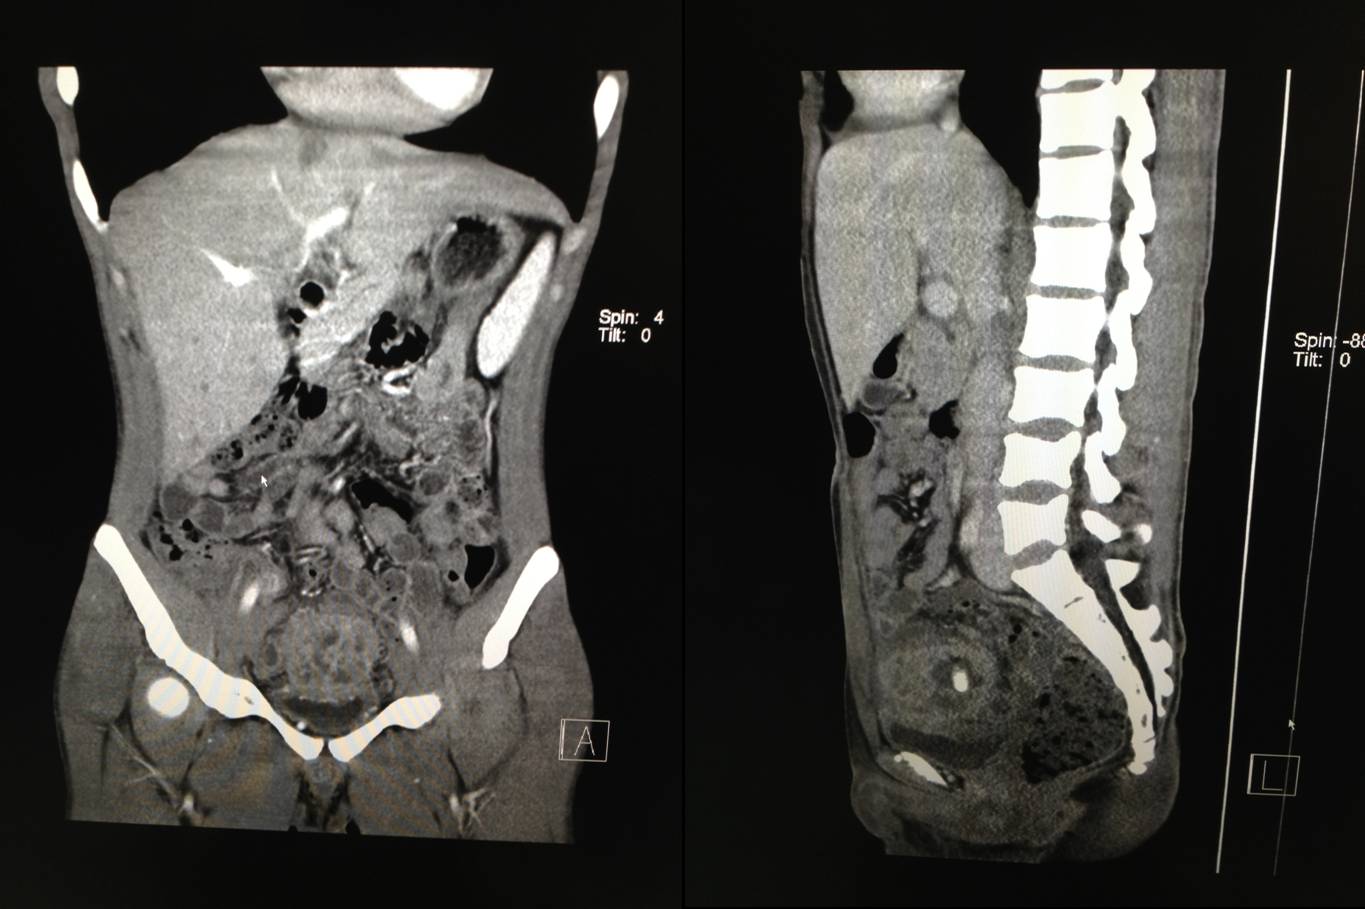

2012.12.20 超声引导下穿刺。

穿刺病理结果:平滑肌组织间大量以淋巴细胞及浆细胞为主的慢性炎症细胞浸润,炎性假瘤可能性大。

讨论:炎性假瘤?属非特异性增生性炎, 表现为纤维结缔组织、血管、上皮细胞和实质细胞增生及淋巴细胞、浆细胞、单核细胞等炎症细胞浸润; 好发于肺、眼眶、肝、脾等处, 起始于腹腔内或腹膜后者罕见; 可发生于任何年龄, 常无明显症状, 多在体检时发现; 病因尚不明确, 可能与自身免疫及感染因素有关。

患者如无腹部手术史和其他病史, 可能为局部自身免疫反应所致。超声声像无特异性, 需与腹膜后特发性纤维化、淋巴瘤和淋巴结转移及恶性纤维组织瘤相鉴别。超声引导下穿刺活检不失为一良好的鉴别方法。